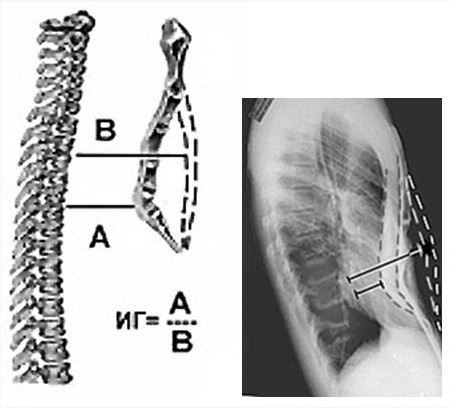

Процедура начинается с получения стандартного рентгеновского снимка, на котором четко видны изменения в костных и мягких тканях грудной клетки. Для измерения глубины деформации специалисты используют определенные ориентиры, например, расстояние между передней поверхностью грудной клетки и внутренними органами, а также угол искривления ребер. Это позволяет точно установить степень отклонения и классифицировать его по шкале, принятой в медицинской практике.

Основные шаги для измерения глубины деформации с помощью рентгеновских снимков включают:

• Получение снимков в нескольких проекциях: для точности измерений часто требуется получить рентгеновские снимки в двух проекциях — боковой и прямой. Это позволяет лучше оценить трехмерное изменение формы грудной клетки.

• Определение глубины воронкообразной деформации: на основе снимков измеряется расстояние между позвоночником и центральной точкой грудной клетки в зоне максимальной воронковидной деформации. Также учитываются данные о наличии отклонений в реберных хрящах.

• Оценка симметрии грудной клетки: на снимках специалист обращает внимание на степень асимметрии, так как это может существенно влиять на выбор метода лечения или операции.